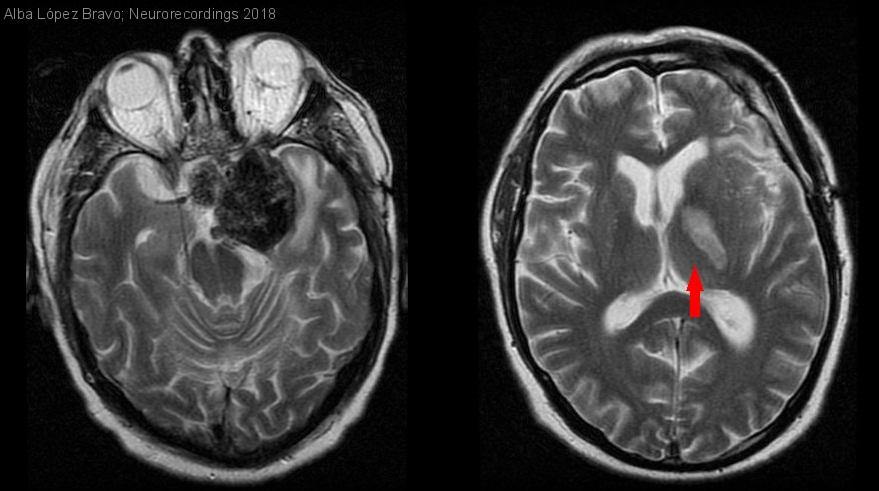

Hombre | 54 años

Diagnóstico final: Ictus isquémico agudo

Se presenta el caso clínico de un varón de 54 años con antecedente de un macroprolactinoma gigante calcificado intervenido en dos ocasiones, con resección parcial de la tumoración. Acude a Urgencias por presentar de forma...